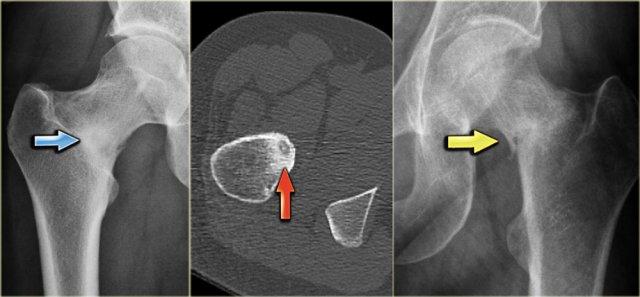

Cần xem xét u sụn ác tính cạnh vỏ xương trong chẩn đoán phân biệt khi phát hiện tổn thương vôi hóa nằm kề cạnh xương vỏ.

Đây là hình ảnh khối u vôi hóa một phần áp sát đầu trên xương cánh tay với sự xâm lấn vỏ xương trên ảnh CT cắt ngang.

Hình ảnh MRI trọng số T2 cho thấy một khối u thùy với cường độ tín hiệu cao.

Khoang tủy xương không bị xâm lấn, điều này rất quan trọng cho chiến lược phẫu thuật.

U sụn màng xương có thể có các đặc điểm hình ảnh tương tự, tuy nhiên, hầu như luôn nhỏ hơn nhiều.

Phim X-quang thường ở một bệnh nhân khác cho thấy tổn thương vôi hóa không đều với hiện tượng nâng cao màng xương và xâm lấn vỏ xương. Bên phải là hình ảnh T2-WI có FS của cùng bệnh nhân. Khối u cạnh vỏ xương có tín hiệu cao và bờ thùy múi. Chẩn đoán phân biệt: sarcoma sụn cạnh vỏ xương, sarcoma xương cạnh màng xương.

Đây là hình chụp X-quang vùng chậu với một ổ di căn tạo xương hầu như không nhìn thấy ở xương chậu trái (mũi tên xanh lam).

Lưu ý rằng CT mô tả các tổn thương này rõ hơn nhiều (mũi tên đỏ).